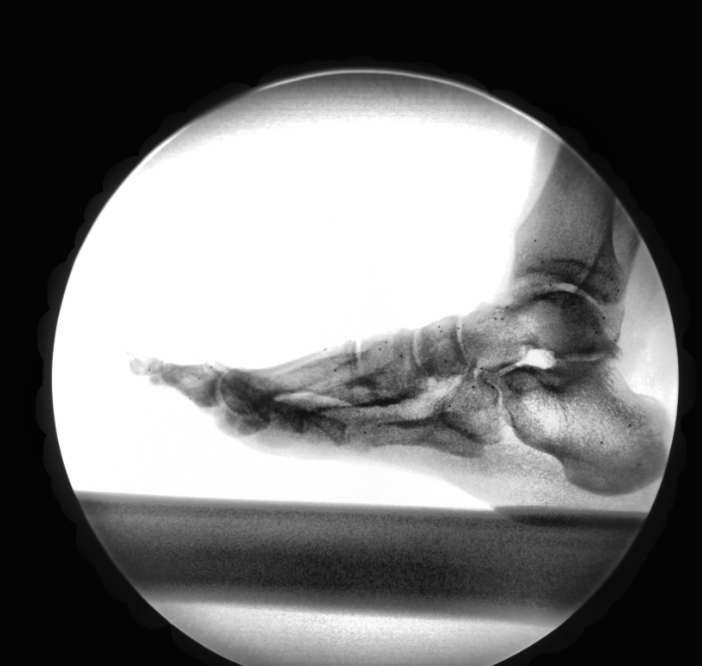

A key proponent of the LIMB Laboratory is the state-of-the-art dual fluoroscopy lab. This system consists of two high-speed video camera, two image intensifiers, and two X-ray sources. This imaging system allows for a precise assessment of dynamic bone translations and rotations.